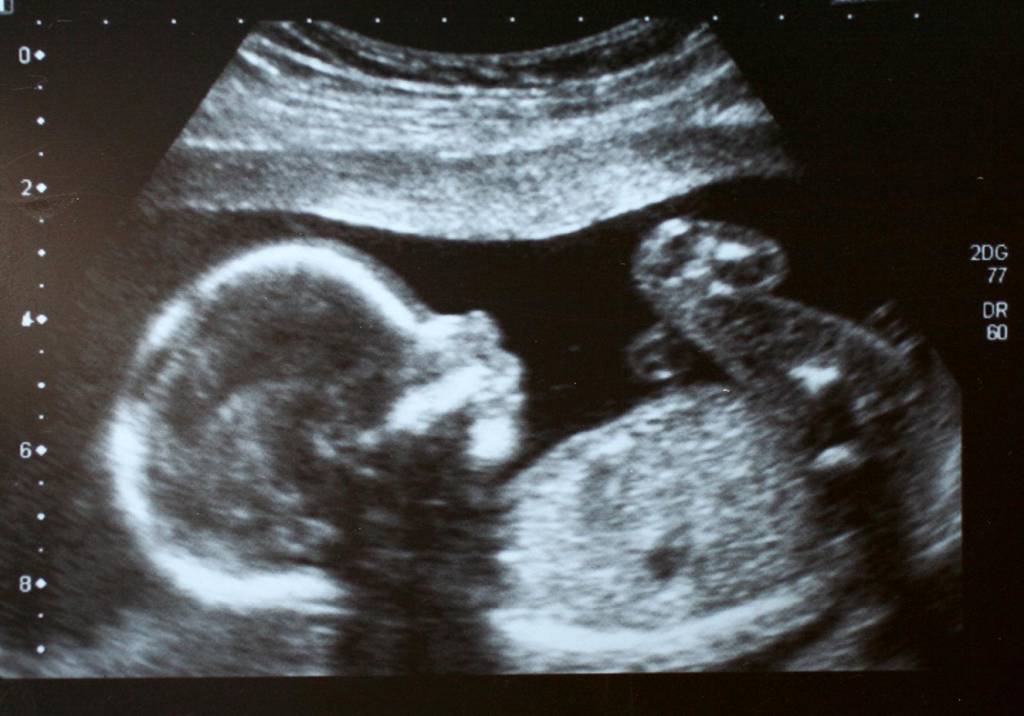

Cardiopatia congênita: por que o diagnóstico é essencial ainda na gravidez

A partir de que semana é possível começar a ouvir o coração do bebê?